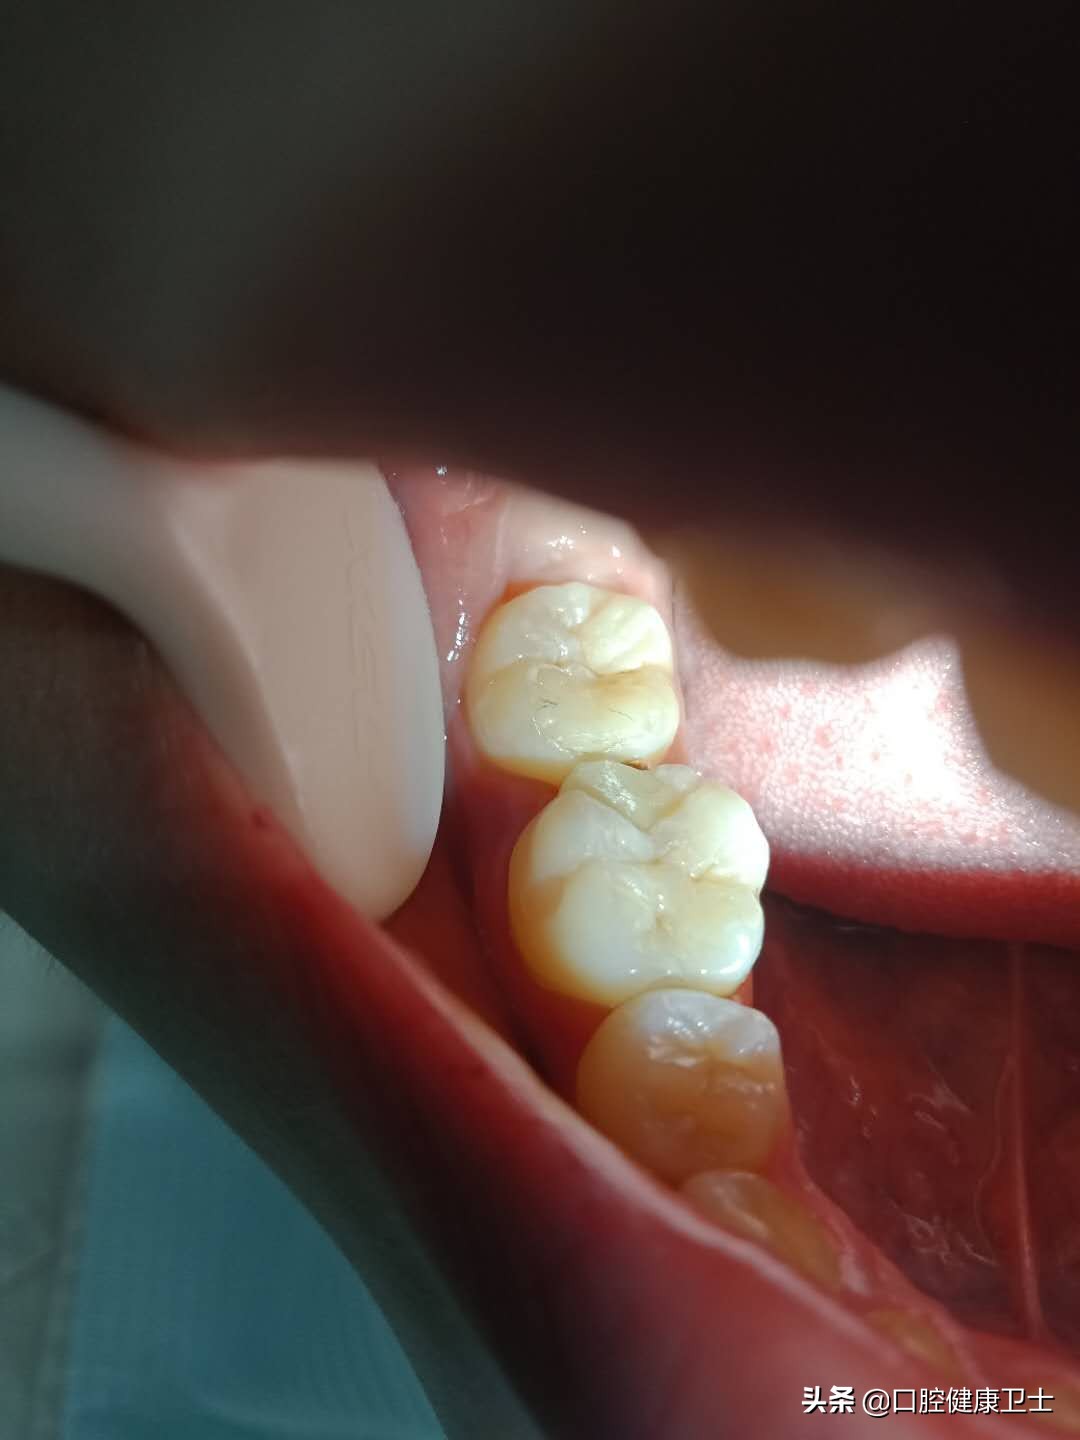

医生:还有问题呢,不仅仅是这些。你看,这张图片更明显,牙齿邻面形态很重要,可你这根本没有把正常邻面形态恢复出来,而是错误的把“牙缝”笼统地堵住了,这就是你出现疼痛的原因。

医生:你这是龈乳头炎,是不良刺激造成的牙龈乳头的炎症反应。就是因为不规范的补牙,把“牙缝”堵住了,压迫了牙龈乳头,引起了龈乳头的发炎。现在需要去除刺激物,就是去除补牙的材料,重新补牙。